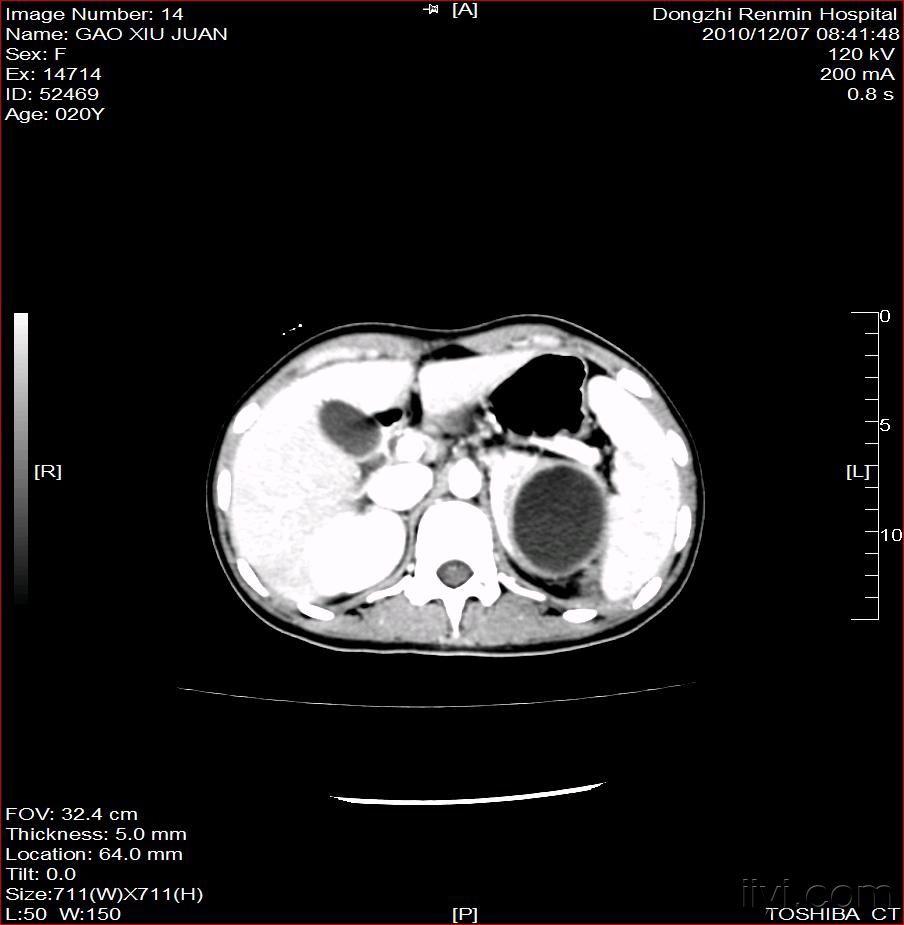

左肾脓肿(附图)

图片尺寸904x925